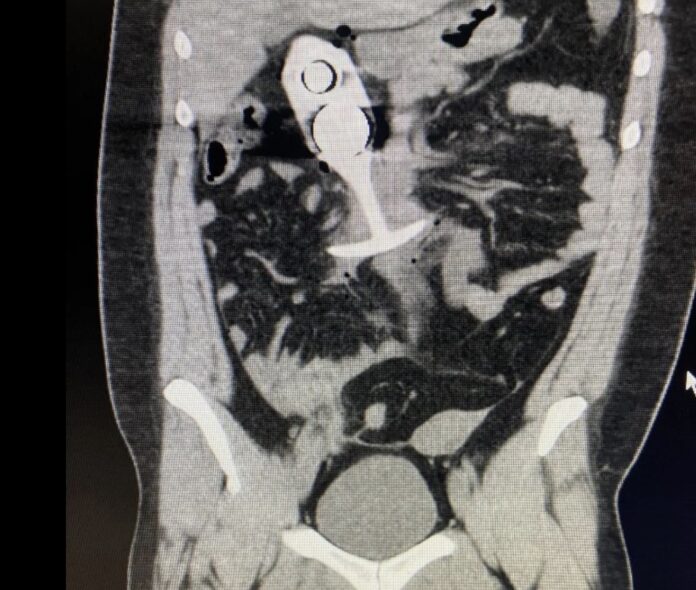

Le noyau métallique de son sextoy a violemment réagi au champ magnétique ultra-puissant de l’IRM et a entamé une ascension express depuis son point d’insertion initial anal jusqu’à sa cage thoracique. Un véritable tremplin anatomique, digne d’une compétition de sports extrêmes, voire d’un grand huit médical.

Dans le cas de Madison, le plug anal aurait atteint une vitesse instantaée proche de celle du son (1235 km/h !) à l’intérieur de son corps !

Après avoir été extirpée en urgence de la machine, Madison a été transportée en soins intensifs. Le plug express avait causé des lésions internes importantes mais, par un rare miracle, aucun organe vital n’a été perforé.

Les chirurgiens ont cependant dû intervenir pour extraire l’objet et soigner les traumatismes internes. D’après les premières analyses médicales, si la vitesse avait été un peu plus élevée, Madison aurait pu subir des blessures mortelles. Une IRM peut en effet transformer un simple objet métallique en projectile létal.

Le professeur Taylor ajoute d’ailleurs que « placer des jouets sexuels ou d’autres objets dans le corps pendant une procédure d’imagerie peut provoquer des artefacts sur l’image, ce qui peut empêcher un diagnostic précis ». Autrement dit, même si votre plug ne décide pas de partir en orbite, il risque de fausser les résultats médicaux.